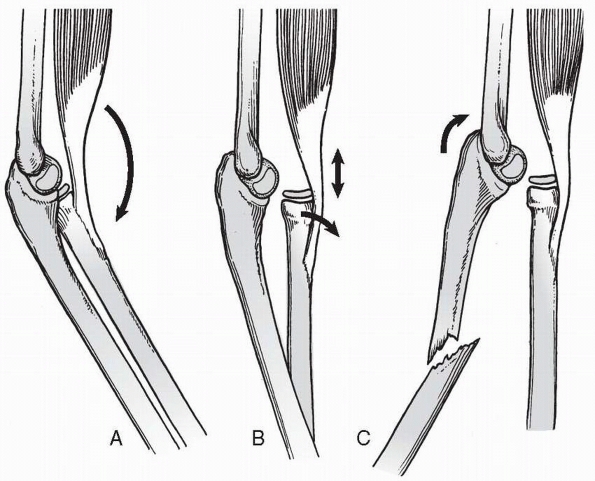

FIGURE 12-1 Bado classification. A.

Type I (anterior dislocation): the radial head is dislocated anteriorly and the ulna has a short oblique or greenstick fracture in the diaphyseal or proximal metaphyseal area. B. Type II (posterior dislocation): the radial head is posteriorly and posterolaterally dislocated; the ulna is usually fractured in the metaphysis in children. C. Type III (lateral dislocation): there is lateral dislocation of the radial head with a greenstick metaphyseal fracture of the ulna. D. Type IV (anterior dislocation with radius shaft fracture): the pattern of injury is the same as with a type I injury, with the inclusion of a radius shaft fracture below the level of the ulnar fracture. |

head associated with an ulnar diaphyseal fracture at any level. This is

the most common Monteggia lesion in children.34,49,75,111

radial head associated with an ulnar diaphyseal or metaphyseal

fracture. This is the most common lesion in adults but very rare in

children.97,98,111

head associated with an ulnar metaphyseal fracture. This is the second

most common pediatric Monteggia lesion.13,44,91,95,143